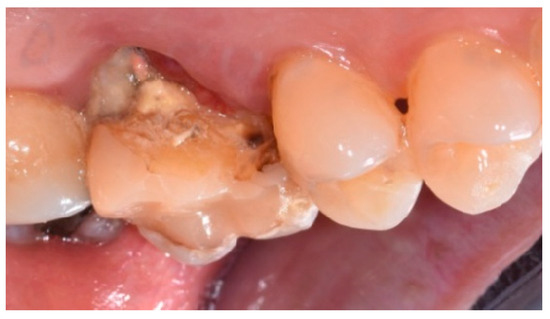

- Cause of extraction: caries, orthodontic reasons, or trauma;

2.4. Surgical Procedure, Evaluation at Follow-Up, and Collection of Radiographic Data